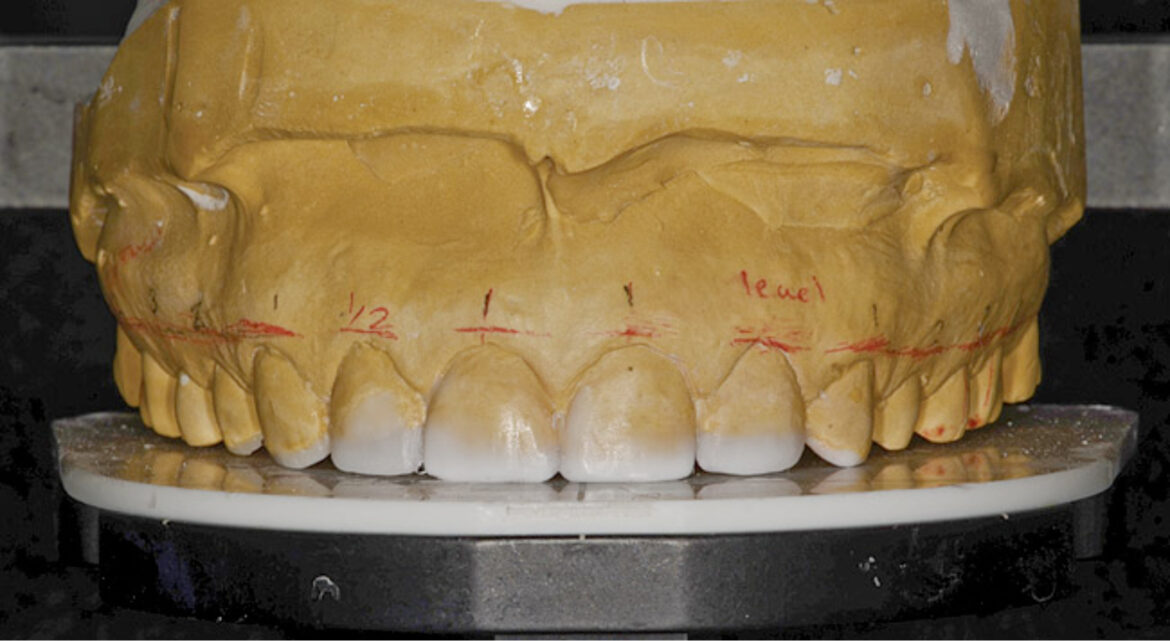

ETAPA a IV-a: Restaurativă

După perioada de vindecare de 4 luni, consecutivă procedurii de alungire coronară, s-au realizat pe modelele montate la noua dimensiune verticală de ocluzie, simulări în ceară complete ale tuturor restaurărilor finale. S-a utilizat silicon chitos pentru a realiza o matrice şi s-a efectuat o machetă pentru pacientă.

După confirmarea clinică a poziţiei marginii incizale maxilare, s-au preparat dinţii de la 1.6. la 2.6. S-a măsurat adâncimea osului la nivelul tuturor dinţilor şi limitele preparaţiilor au fost realizate respectând indicaţiile pentru acest tip fiziologic de complex creastă osoasă – dinte – ţesut gingival, evitându-se astfel lezarea inserţiei epiteliale. S-au confecţionat restaurări provizorii în trei regiuni dentare, au fost inserate în cavitatea bucală şi adaptate în RC. S-au înregistrat apoi relaţiile intermaxilare pentru a fi trimise în laboratorul de tehnică dentară.

S-a înregistrat amprenta funcţională, iar restaurările provizorii au fost cimentate. După o perioadă de 5 zile şi reevaluarea relaţiilor ocluzale funcţionale, s-au efectuat: înregistrarea cu arc facial cu ajutorul analizatorului dento-facial Kois, amprenta restaurărilor provizorii şi fotografiile acestora. Toate au fost ulterior trimise în laboratorul dentar (fig. 11).